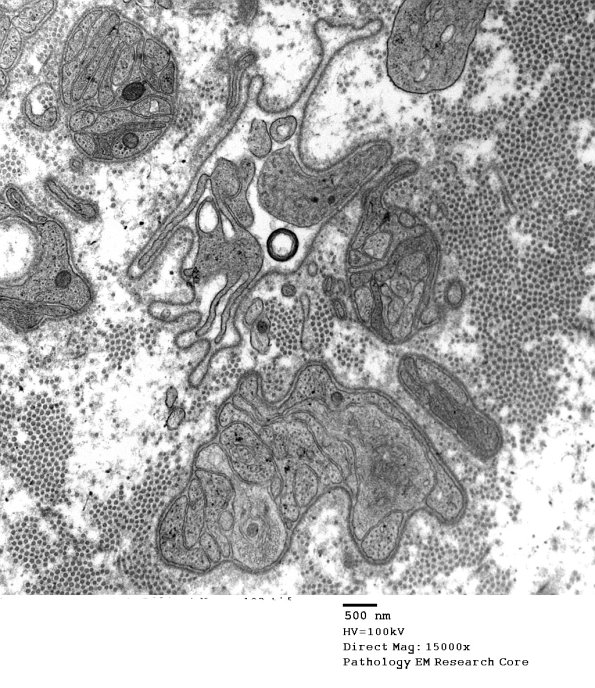

2F4,5 In some cases bands of Büngner lose Schwann processes with time and few processes remain within corregated basement membranes. (electron micrographs)